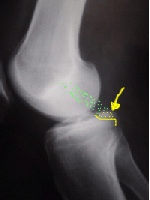

Mesure de la laxité par testing radio

La laxité (facteur diagnostique et pronostique) peut être mesurée par des radios comparatives de profil avec poussée antérieure sur le tibia.

La fracture de l'épine tibiale postérieure

La radio simple peut aussi montrer une fracture de l'épine tibiale postérieure par traction par le LCP qui au lieu de se rompre, arrache son insertion osseuse.